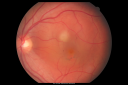

Serpiginouse Choroiditis (Chorioretinitis) - Acute Right Eye - Old Left Eye VA 20/25 OD , 20/50 OS820 views63-year-old woman has serpiginous choroiditis (date - March 2011). The right eye has not been previously involved, and then she noticed new onset floaters in the right eye for the last two weeks. Her vision in the right eye is hazy because of that.

VISUAL ACUITY: Vision OD is 20/25, OS is 20/50